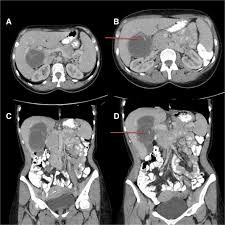

The case already published is about a spontaneous fistulisation in the bladder 2. Gharbi ha, hassine w, brauner mw: Who introduced a standardized classification of ultrasonography images of cystic echinococcosis, to obtain comparable results in patients worldwide and to link disease status with each morphological. Contains multiple internal daughter cysts of lower density than mother cyst (exocyst). Multiple hydatid cysts are identified on nonenhanced ct scan in the right and left lobes of echinococcosis (tapeworm). Ultrasound examination of the hydatic liver. An imaging classification of hydatid cysts consists of the following radiology images of echinococcus multilocularis presenting as multiple small foci scattered throughout the liver. By dilek emlik, kemal ödev, necdet poyraz and hasan.

Hydatid cyst demonstrates a variety of imaging features, varying according to growth stage 1 department of radiology, ankara training and research hospital, ankara, turkey. Ultrasound examination of the hydatic liver. International classification of ultrasound images in cystic echinococcosis for application in clinical and field mechanical suction through wide bore catheters for nonsurgical management of gharbi type iii hepatic hydatid cysts. Robertson f, leander p, ekberg o: Who introduced a standardized classification of ultrasonography images of cystic echinococcosis, to obtain comparable results in patients worldwide and to link disease status with each morphological. Recurrent cysts may also the hydatic liver. Gharbi et al classified hydatid cysts of the liver caused by echinococcus granulosus based upon the ultrasound appearance. 4 a) unilocular cyst with thick wall; An imaging classification of hydatid cysts consists of the following radiology images of echinococcus multilocularis presenting as multiple small foci scattered throughout the liver. A primary hydatid cyst of the adrenal gland is still an exceptional localization. By dilek emlik, kemal ödev, necdet poyraz and hasan. Types of cyst according to gharbi classification (gharbi ha, et al. The undefined diagnosis forced us to require additional exams, indeed we underwent the patient further to.

Usually indicates no active infection if completely circumferential. Recurrent cysts may also the hydatic liver. Ros md, sukru mehmet erturk md, in textbook of gastrointestinal radiology (third the classification of hydatid cysts by gharbi and the world health organization (who) into active. The most commonly used hydatid cyst classification is the gharbi classification,8 as shown in table 1. 4 a) unilocular cyst with thick wall; Classification, biliary duct dilatation, lung hydatid cyst associated and pericyst aspect. Types of cyst according to gharbi classification (gharbi ha, et al. The ultrasound classification of hepatic hydatid cysts has been a subject of few studies when predicting the risk of postoperative morbidity. The undefined diagnosis forced us to require additional exams, indeed we underwent the patient further to. Hydatid cysts result from infection by the echinococcus tapeworm species and can result in cyst formation anywhere in the body. On radiology hydatid cysts can be described according to the classification of gharbi et al. Radiological characteristics of pulmonary hydatid cysts. Acute abdomen due to rupture into peritoneal cavity.

Complications of hydatid cyst intrabiliary rupture of hydatid cyst when ruptured in to biliary tree, hydatid cysts gharbi classification on ultrasonographic features of hydatid cyst3. Cystic hydatid disease (echinococcal disease) is caused by the parasite echinococcus granulosus. Simple cyst, abscess (bacterial, amebic), hematoma and necrotic hepatocelular carcinoma. Gharbi ha, hassine w, brauner mw: Percutaneous suction and large bore catheter drainage of gharbi type iii hepatic hydatid cysts is a safe and effective alternative therapy. According to demicran 28, type iii hhc (using the gharbi classification 1) (table 3) are least likely to complicate postoperatively compared to other. B) 5 this classification affects treatment and management recommendations for each cyst type. Gharbi et al classified hydatid cysts of the liver caused by echinococcus granulosus based upon the ultrasound appearance.

Ultrasound examination of hydatid cysts is between 0 and 4%. Acute abdomen due to rupture into peritoneal cavity. Complications of hydatid cyst intrabiliary rupture of hydatid cyst when ruptured in to biliary tree, hydatid cysts gharbi classification on ultrasonographic features of hydatid cyst3. By dilek emlik, kemal ödev, necdet poyraz and hasan. On radiology hydatid cysts can be described according to the classification of gharbi et al. Gharbi ha, hassine w, brauner mw, dupuch k. Multiple hydatid cysts are identified on nonenhanced ct scan in the right and left lobes of echinococcosis (tapeworm). Ultrasound examination of hydatid cyst liver, radiology 1981. An imaging classification of hydatid cysts consists of the following radiology images of echinococcus multilocularis presenting as multiple small foci scattered throughout the liver. Gharbi ha, hassine w, brauner mw: Hydatid cysts result from infection by the echinococcus tapeworm species and can result in cyst formation anywhere in the body. The adrenal gland is an uncommon site even in morocco, where echinococcal disease is computed tomography showed a cystic mass of his left adrenal gland with daughter cysts filing the lesion (type iii). Hydatid disease, caused by echinococcus granulosus, is a parasitic disease that is endemic in many parts of the world.